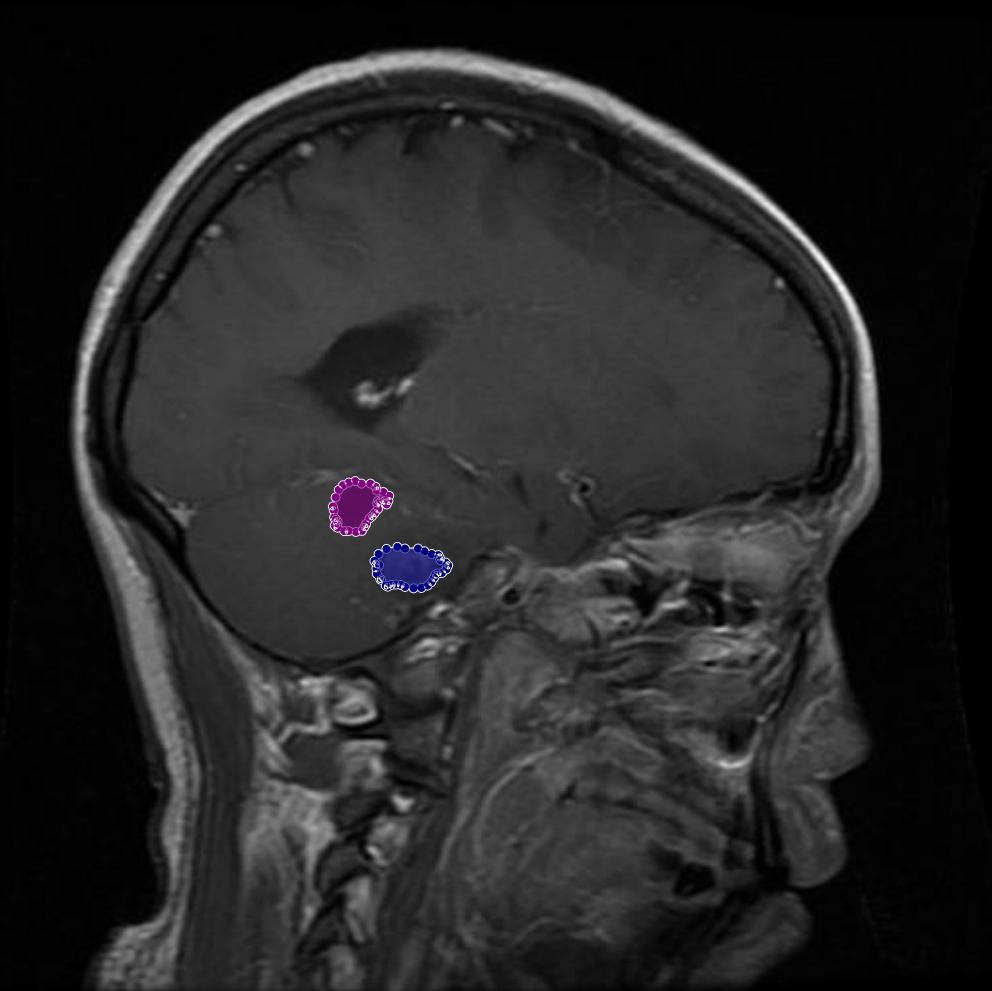

Conversely, there were cases where genuine tumor regions had been overlooked during the initial annotation process. With input from the Physician and radiologist, these missing regions were added to the annotations, ensuring that the masks comprehensively captured all tumor areas. Figure 7 demonstrates an example of such an adjustment, where previously unannotated tumor segments were correctly incorporated into the final mask.

Figure 7: Samples of partial-region underannotations. The purple area indicates regions that were initially marked as non-tumorous but were later identified by the radiologist and physician as tumorous.